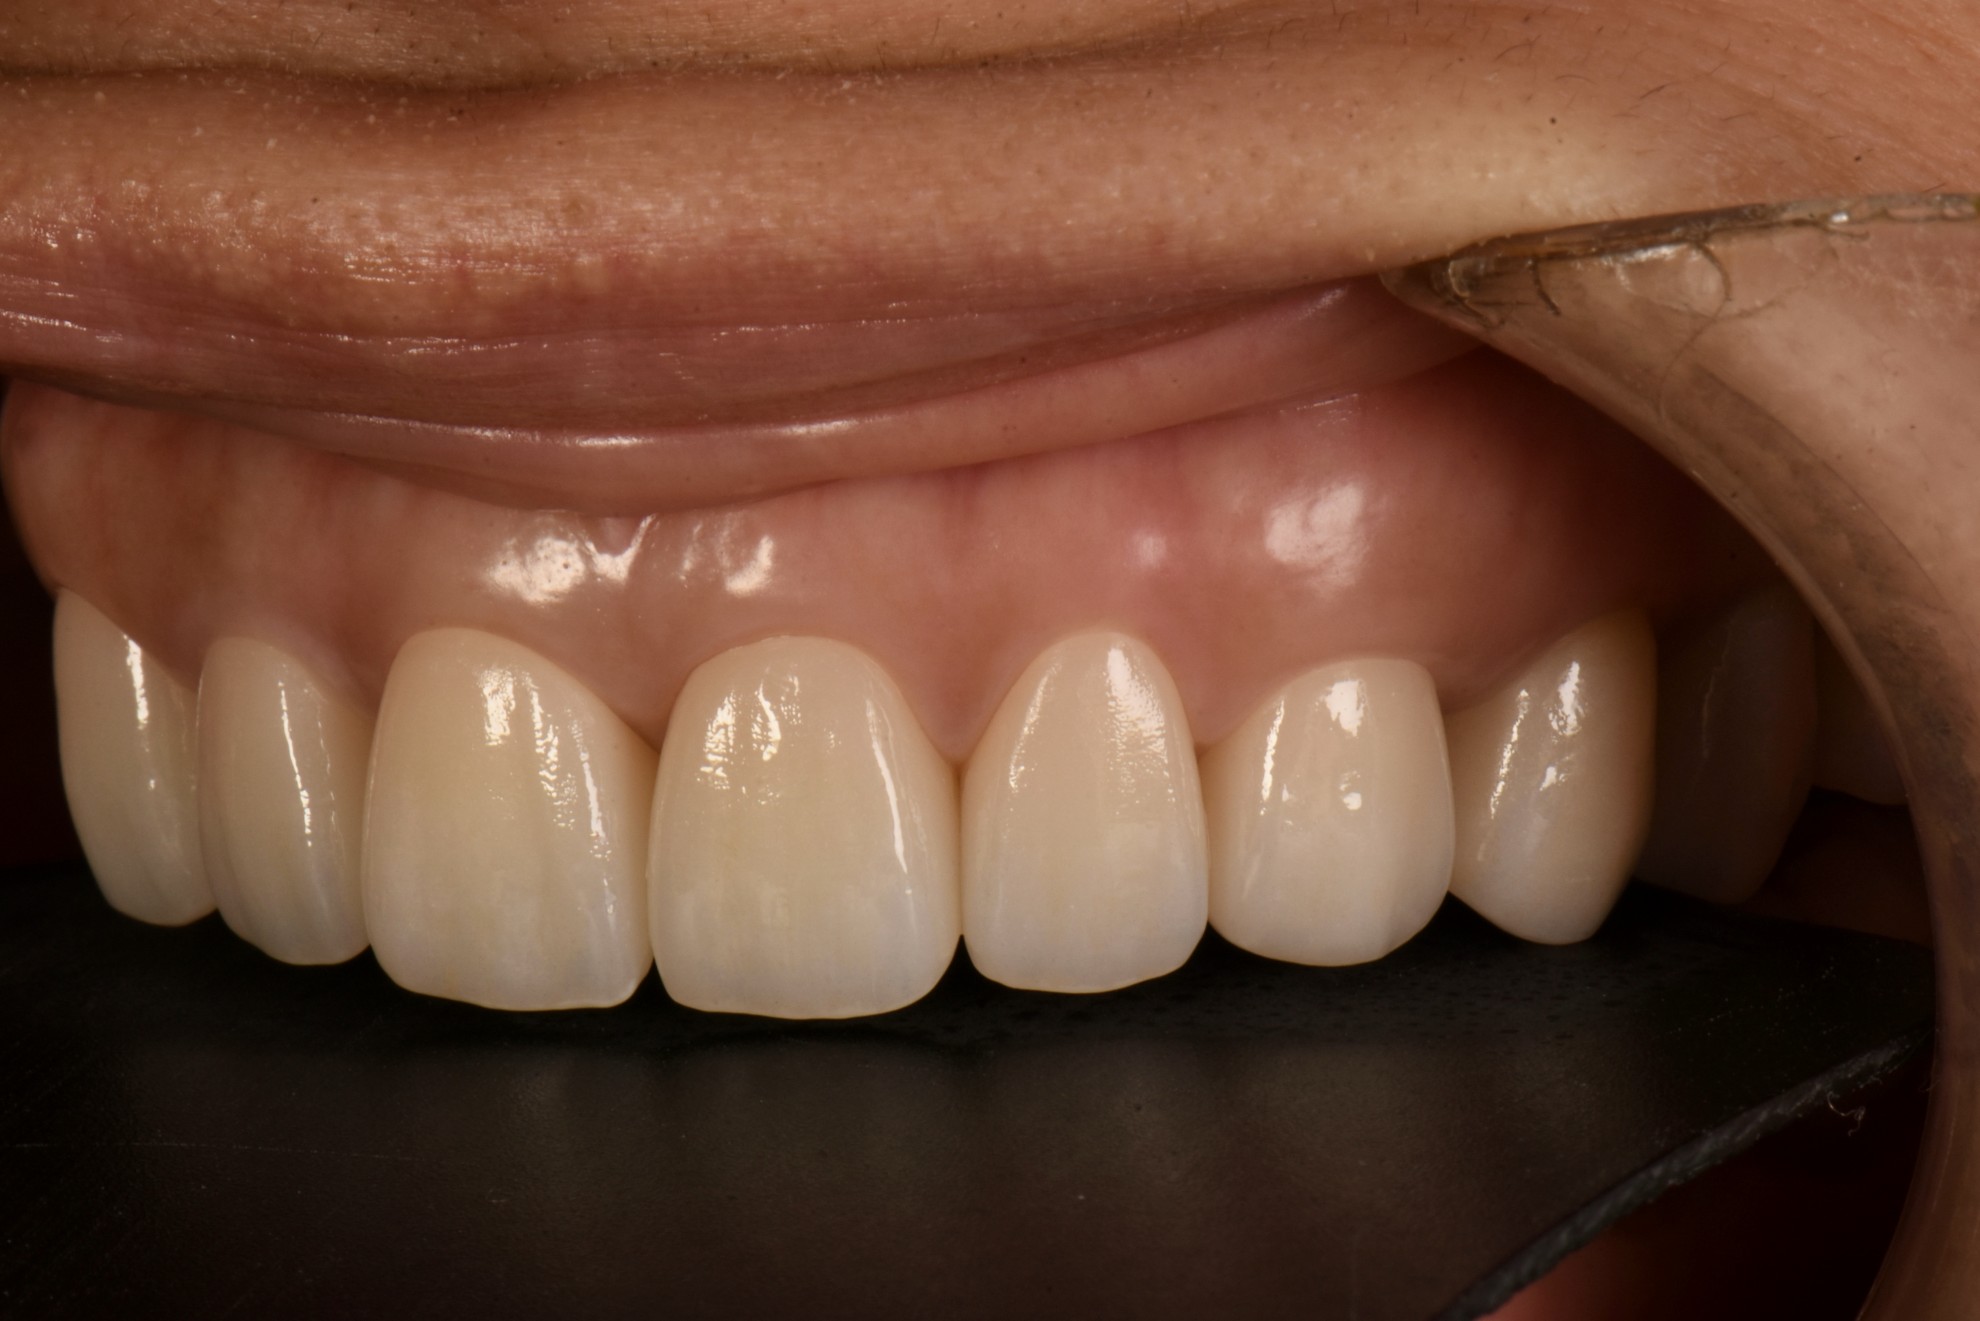

治療後

案例一